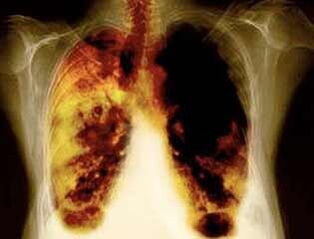

- Zmniejszenie ryzyka rozwoju raka płuc i wielu innych rodzajów raka.

- Zmniejszenie ryzyka rozwoju niektórych chorób płuc (na przykład przewlekłej obturacyjnej choroby płuc).

- Po 1-9 miesiącach odbywa się kaszel i duszność oddechu: rzęski (małe włosy) zaczynają normalnie leczyć śluz, oczyszczając płuca i zmniejszając ryzyko zakażenia.

- 10 lat po zaprzestaniu palenia o 40%prawdopodobieństwo raka płuc zmniejsza się o 40%.